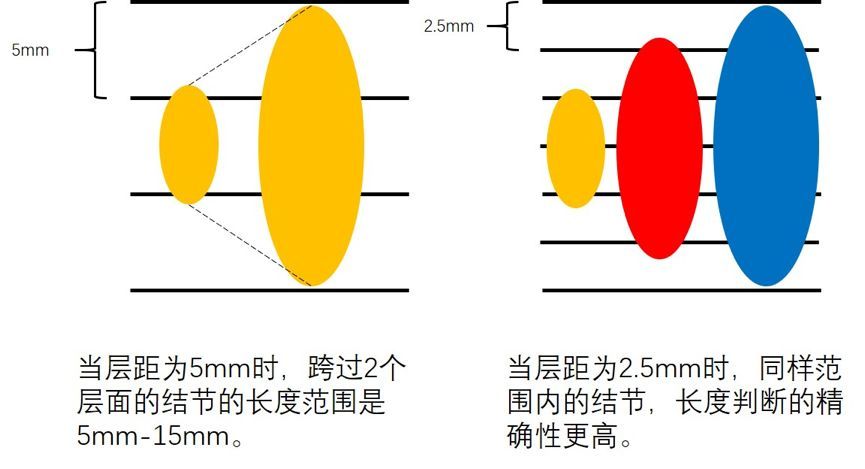

CT的层距越小,对于判断肺小结节的大小更精确,请看下图。